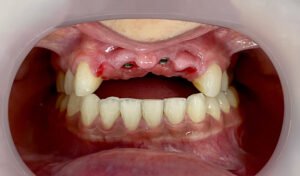

Hoy, gracias a mi prótesis híbrida, puedo reír, comer y hablar con total naturalidad. Recuperé mi sonrisa, mi confianza, mi alegría. Hoy puedo decir que recupere mi calidad de vida